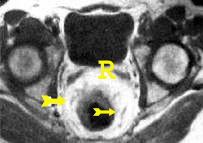

תהודה מגנטית (MRI)

בדיקת תהודה מגנטית (MRI) הוכנסה בשנים האחרונות ככלי נוסף להערכת שאתות כרכשתיות-חלחולתיות (Colorectal). ההדמיה המגנטית מאפשרת לקבל חתכים סגיטליים ואקסיאליים, וכן להבדיל בין שאת לרקמה צלקתית או תקינה. הבדיקה אינה דורשת מתן חומר ניגוד כמו בטומוגרפיה ממוחשבת.